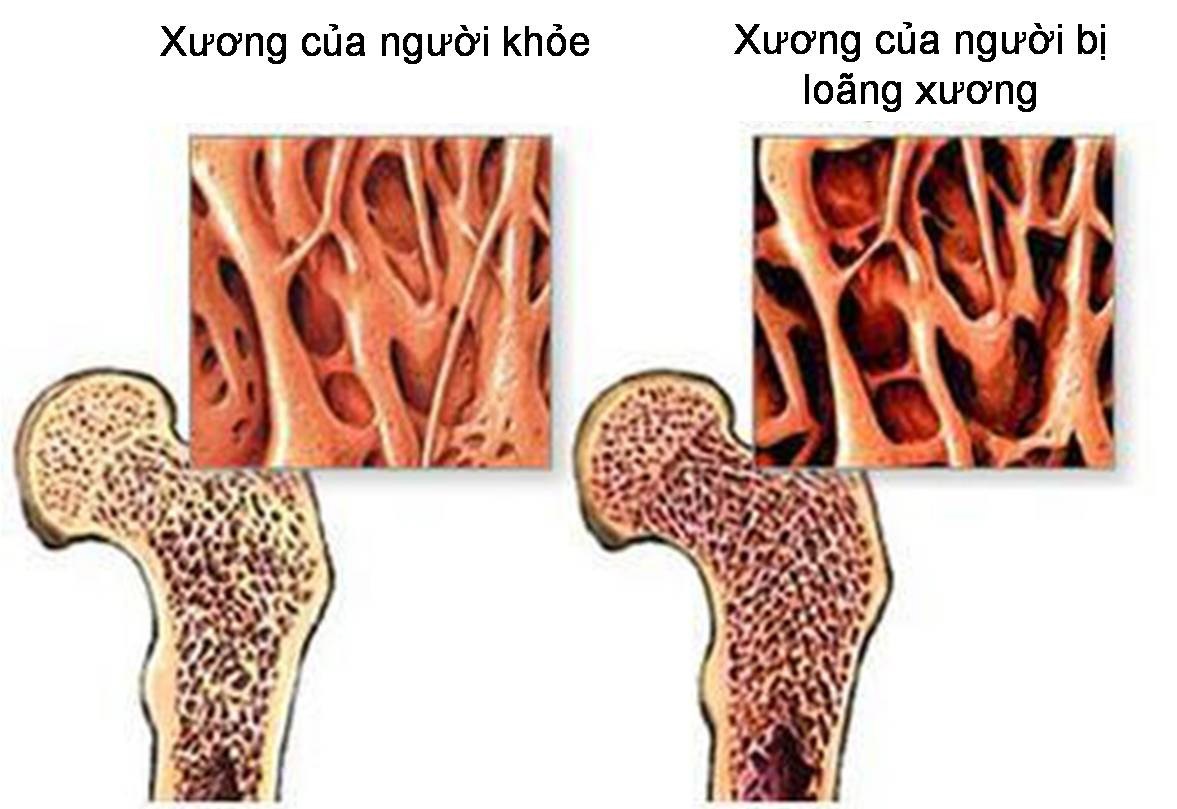

Cùng với quá trình lão hóa, hệ xương của con người trải qua sự suy giảm tự nhiên về mật độ khoáng, cấu trúc và độ bền. Đây là yếu tố nền dẫn đến loãng xương – tình trạng xương trở nên giòn, dễ gãy, đặc biệt ở các vị trí như cột sống, cổ xương đùi và cổ tay. Để duy trì xương chắc khỏe, việc chăm sóc dinh dưỡng và tập luyện là vô cùng quan trọng.

Theo các tổ chức y tế quốc tế, nguy cơ loãng xương tăng rõ rệt sau tuổi 50, nhất là ở phụ nữ sau mãn kinh do giảm estrogen. Không chỉ yếu tố tuổi tác, nhiều thói quen sống hằng ngày cũng tác động trực tiếp đến sức khỏe xương.

Nguy cơ loãng xương tăng rõ rệt sau tuổi 50, nhất là ở phụ nữ sau mãn kinh do giảm estrogen.

Sức khỏe xương không chỉ liên quan đến nguy cơ gãy xương mà còn ảnh hưởng trực tiếp đến khả năng vận động và mức độ độc lập của người cao tuổi. Khi xảy ra gãy xương, đặc biệt là gãy xương hông, người bệnh có thể phải đối mặt với thời gian hồi phục kéo dài, thậm chí mất khả năng tự chăm sóc. Vì vậy, việc ưu tiên bảo vệ xương ngay từ sau tuổi 50 là cần thiết.